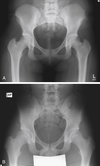

DASHBOARD

- Fracture of the posterior rim of the acetabulum

- a seated passenger striking the knee on a dashboard, driving the head of the femur into the acetabulum